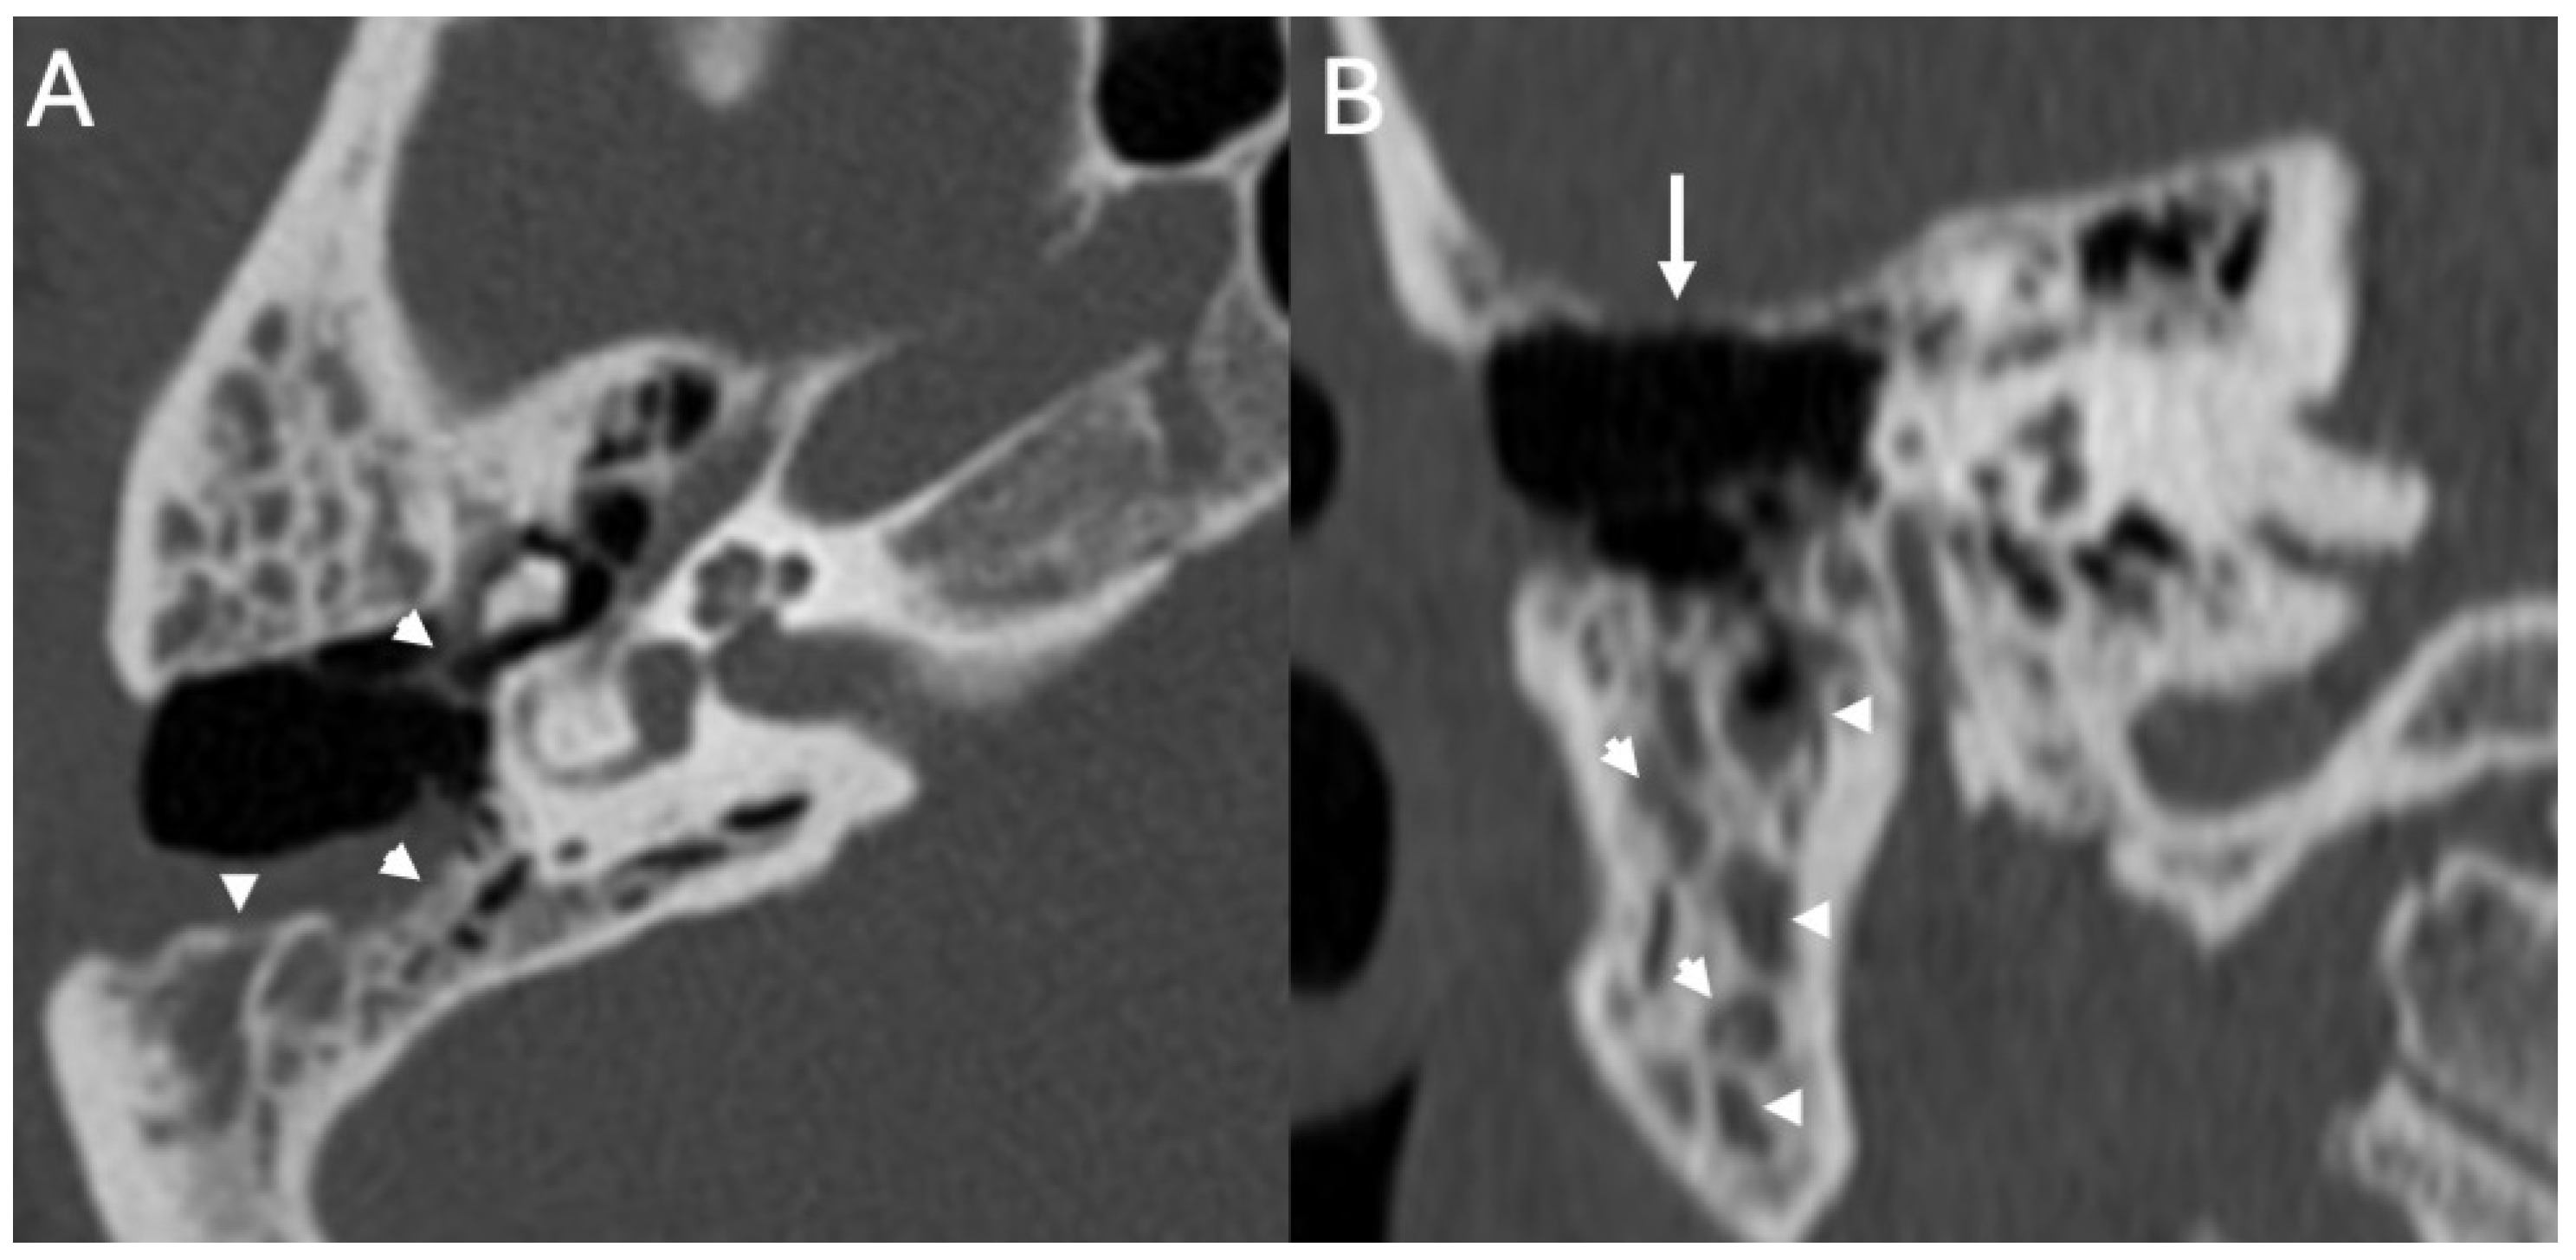

3.2. Bony Dehiscence

3.3. Cholesteatoma

| Bony Dehiscence/Temporal Bone Defects | Barbara et al., 2022 [22]; Sanna et al., 2009 [23]; Lim et al., 2012 [24]; Rabiei et al., 2025 [25] | Case-based studies and reviews | Tegmen tympani or semicircular canal defects create a route for meningitis and meningoencephalocele; HRCT coronal reconstructions preferred. |